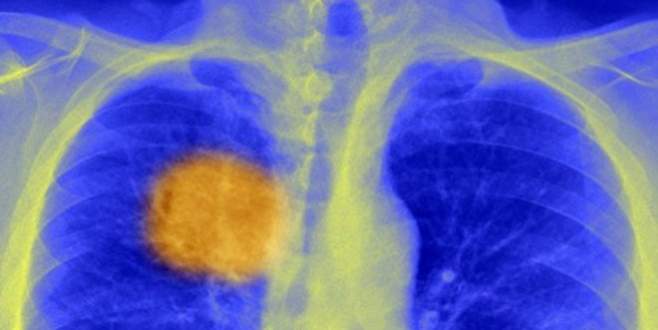

Kanserin ‘zayıf noktası bulundu’

Bilim insanları, bağışıklık sistemini kanseri yok etmeye yönlendirecek bir metod bulduklarına inanıyorlar.